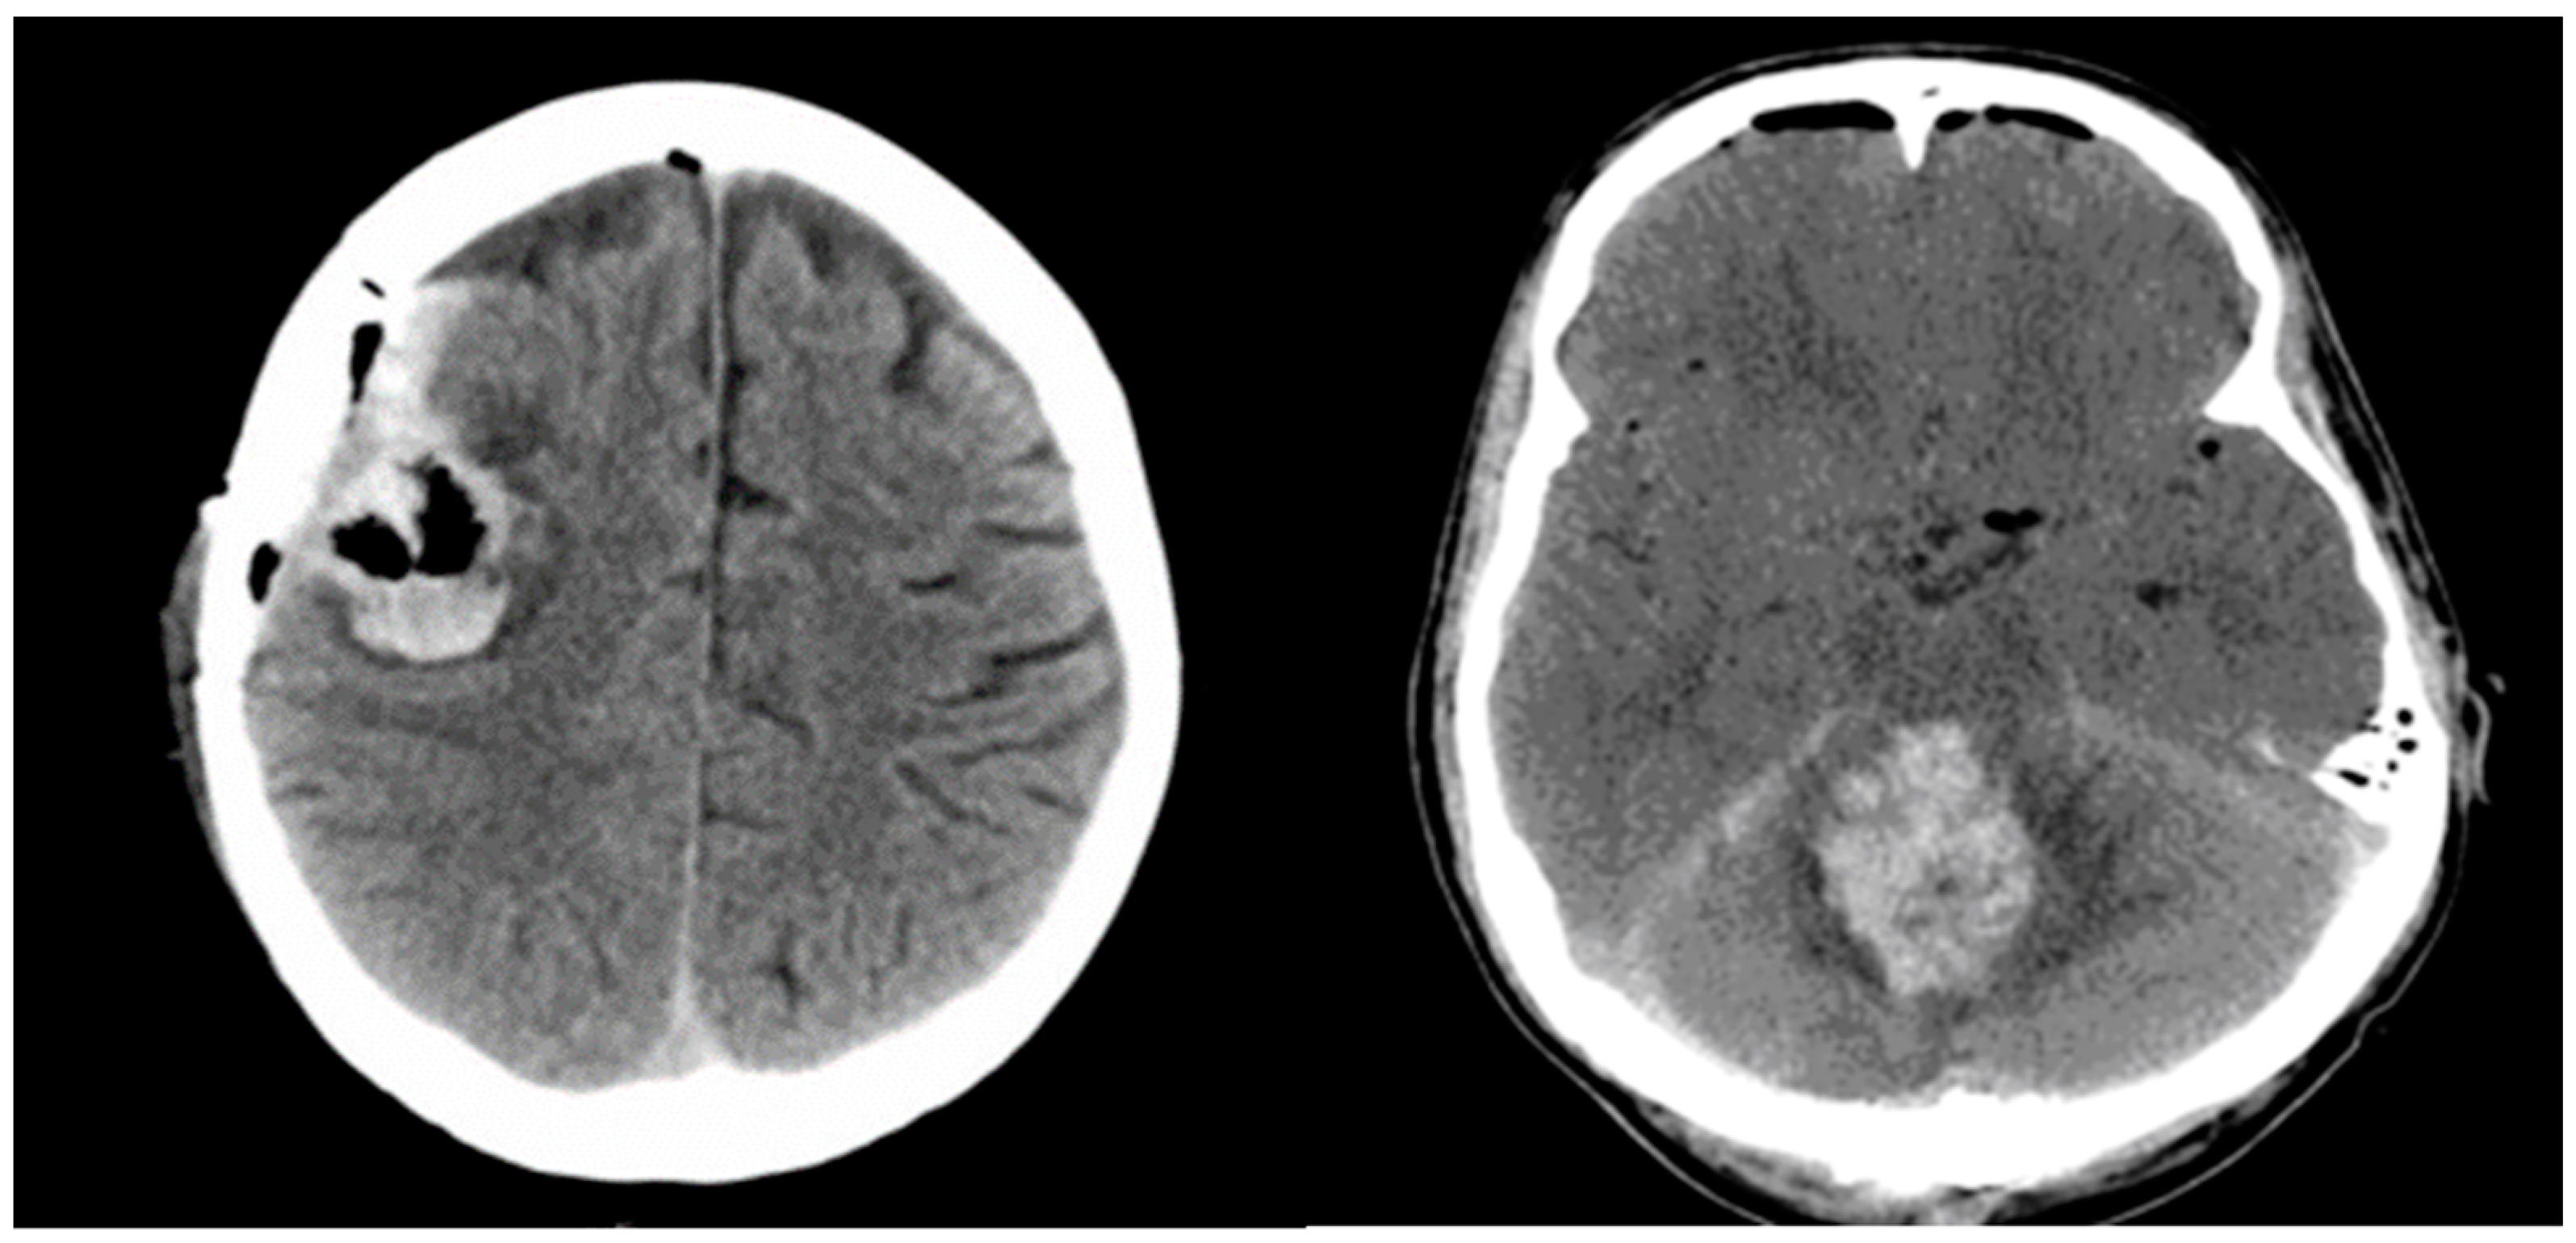

Significant postoperative hemorrhage was defined as bleeding that led to notable neurological symptoms, such as increasing intracranial pressure and space-occupying effects requiring surgical intervention. Symptomatic neurological deficits included focal neurological deficits, headaches, vomiting/nausea, or changes in cognitive function. Figure 2 illustrates two cases of postoperative hemorrhage that required reoperation.

Figure 2.

Illustrates two cases of postoperative hemorrhage that required reoperation.